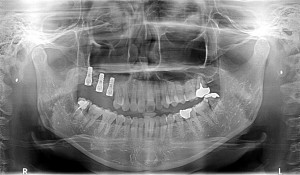

右下3番4番5番が欠損されている方でした。

CT画像を拝見すると十分な骨の確認が出来ましたので

スイス製ストローマンインプラントRN

直径4.1mm、長さ10mmを二本埋入させて頂きました。

二ヵ月後には最終補綴物を装着する予定です。